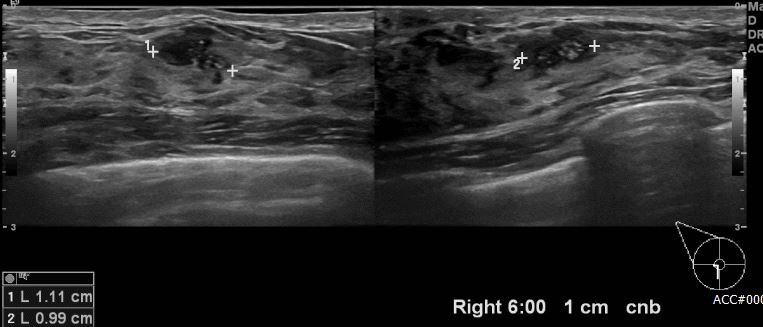

상기환자 좌측 유방암으로 진단받아 치료 중이신 40대 여성 분으로 타원 검진상 우측 6시 방향에서 1cm 떨어진 거리의 의심스러운 멍울 조직검사 시행하여 우측 침윤암 진단 되었습니다.